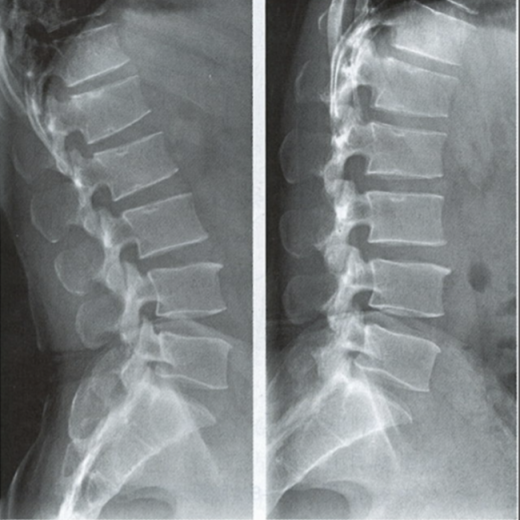

腰椎動(dòng)力位,也稱為過屈過伸位,可以理解為兩個(gè)極限體位下的側(cè)位片,腰椎動(dòng)力位通過做最大程度彎腰(過屈)和后仰(過伸)的動(dòng)作拍攝側(cè)位片,來觀察腰椎在極限活動(dòng)下的表現(xiàn)。如果說腰椎側(cè)位片能靜態(tài)體現(xiàn)椎體的解剖學(xué)結(jié)構(gòu)、序列及生理曲度改變,那么腰椎動(dòng)力位則是評(píng)估腰椎動(dòng)態(tài)功能性的檢查。

腰椎過伸位:是指腰部盡可能向后伸展,以雙髖關(guān)節(jié)位支撐點(diǎn),運(yùn)動(dòng)前后骨盆位置無改變。腰椎過伸時(shí),向前的曲度大于生理曲度,上部向后傾斜。

腰椎過屈位:是指腰部盡可能向前彎曲,以雙側(cè)髖關(guān)節(jié)位支撐點(diǎn),運(yùn)動(dòng)前后骨盆位置無改變。腰椎過屈的表現(xiàn)位向前的曲度減小、變直,上部向前傾斜。

當(dāng)1度及以上的滑脫時(shí)才可以在普通腰椎側(cè)位上觀察到,而1度以下的滑脫或失穩(wěn)則在普通側(cè)位片上難以發(fā)現(xiàn),這時(shí)候就需要借助腰椎動(dòng)力位進(jìn)行診斷。

腰椎動(dòng)力位 左圖為過伸位、右圖為過屈位